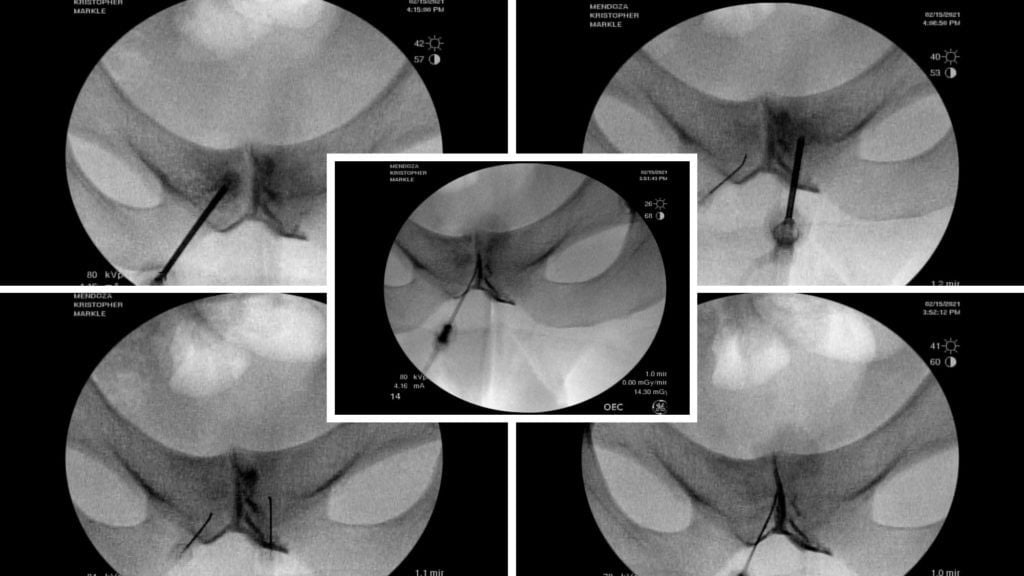

Physicians in the licensed Regenexx network use advanced imaging techniques, such as fluoroscopy, to precisely target affected areas, supporting the potential benefits of these procedures.

Fluoroscopy-guided imaging demonstrated the precise delivery of the patient’s own bone marrow concentrate into the deteriorating bone surrounding the symphysis pubis and into the degenerated joint itself. This approach designed to support healing, may help reduce inflammation, and may help promote stability in the affected area.